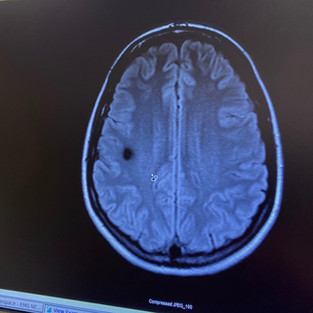

This photo is a picture of my “little friend” on the left. Lately, it’s been my enemy, but why be negative😝? It’s a non-cancerous Angioma Cavernoma Malformation. It is the size of a quarter and goes deeper down. It’s a sporadic. Meaning, not hereditary. Finding that out recently was a huge relief considering our family history and that there are 3 genetic mutations.

The picture on the right is me meeting with the world renown, Dr. Awad, at Universirty of Chicago Medicine. Cavernomas is his specific area of medicine and research. He has me in one of his studies now and is on his way to helping me accurately. He told me he can remove my Cavernoma, no problem. I’m still praying about this as it’s a major surgery and recovery. Timing for that is up to the Lord’s best plan for my life. I also pray for miracles to avoid surgery.